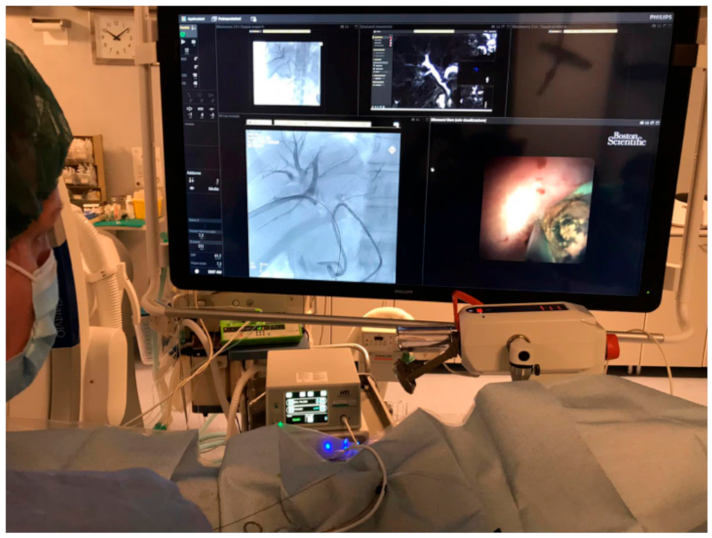

2.3. Technique and Procedure

3. Results